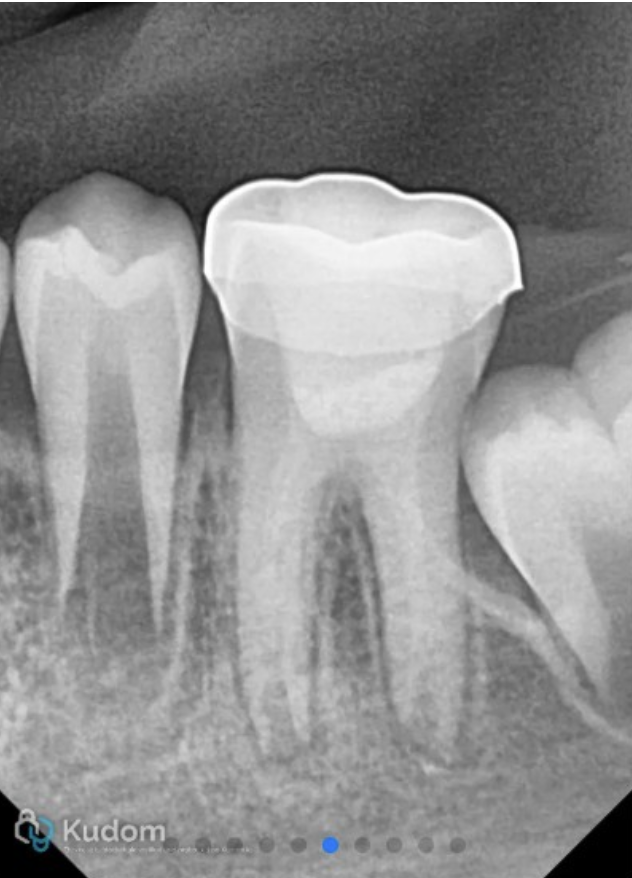

Radiograph of 36 showing Biodentine® in canals and access closed with composite.

Fig. 4

The canals and chamber were then thoroughly dried with paper points and Biodentine® (Septodont, Saint-Maur-des-Fossés, France) was placed into the canals and up to the working length in small increments and gently condensed with a hand plugger. A resin modified GIC liner was used to close off the canal orifices, followed by restoration of coronal seal with composite build-up.